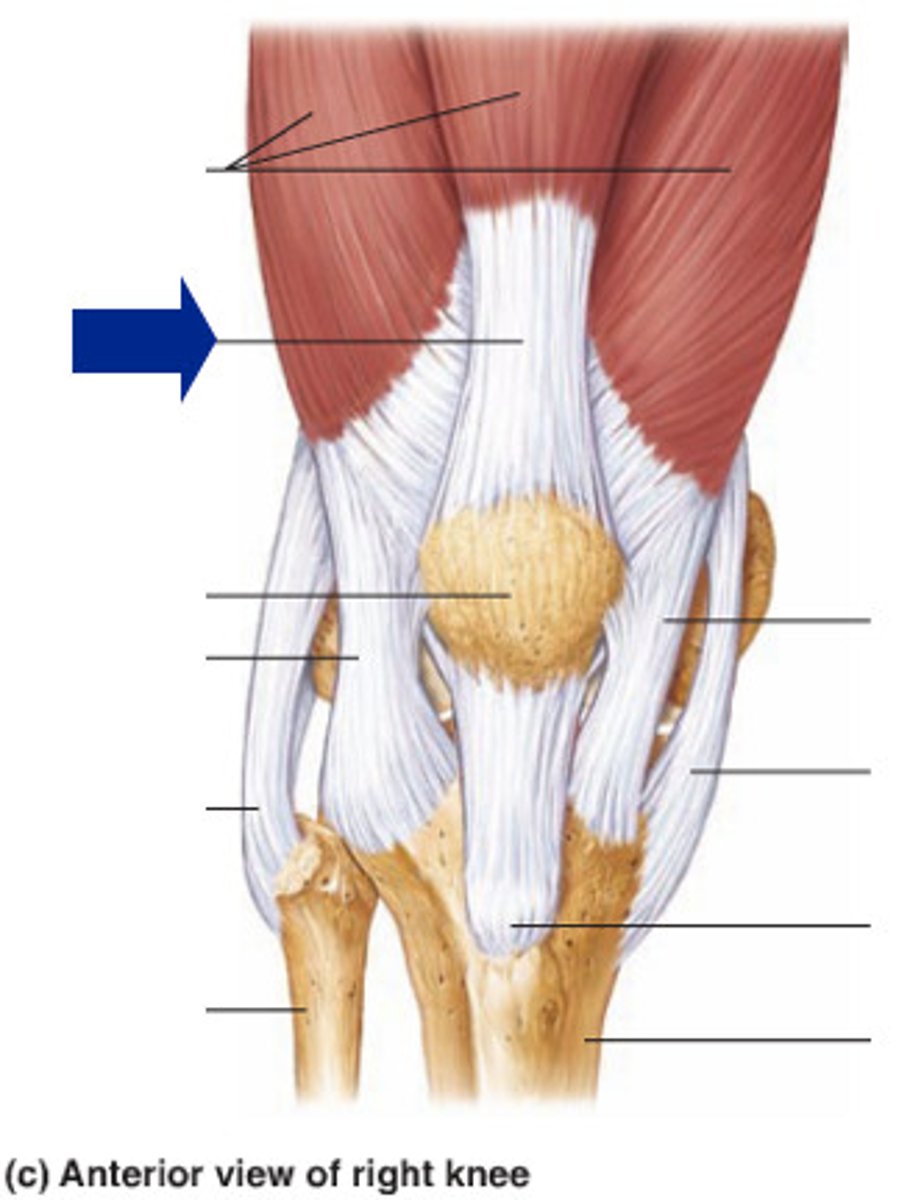

Quadriceps tendon

Patellar ligament

Medial meniscus

Lateral meniscus

Anterior cruciate ligament

Posterior cruciate ligament

Medial (tibial) collateral ligament

Lateral (fibular) collateral ligament